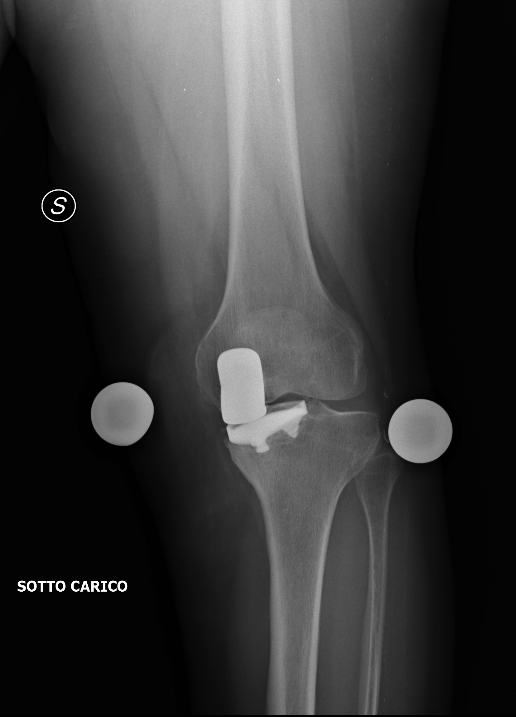

-degenerazione dei compartimenti articolari residui: le protesi monocompartimentali, per definizione, sostituiscono un solo compartimento articolare, più spesso quello mediale. Questo significa che in seguito è teoricamente possibile che uno dei due compartimenti residui, femorale o tibiale, vada incontro ad un processo artrosico tale da richiederne la sostituzione protesica. In questi casi la soluzione più validata è la conversione a protesi totale.